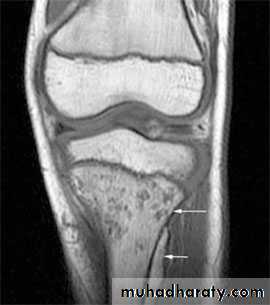

MRI: Detect marrow changes secondary to infection at early stage & help in evaluation of potential spread of infection to adjacent bone or joint.

• MRI:

• Determine the size and the location of the soft tissue component (i.e lymphadenitis, cold abscess formation, marrow changes.)